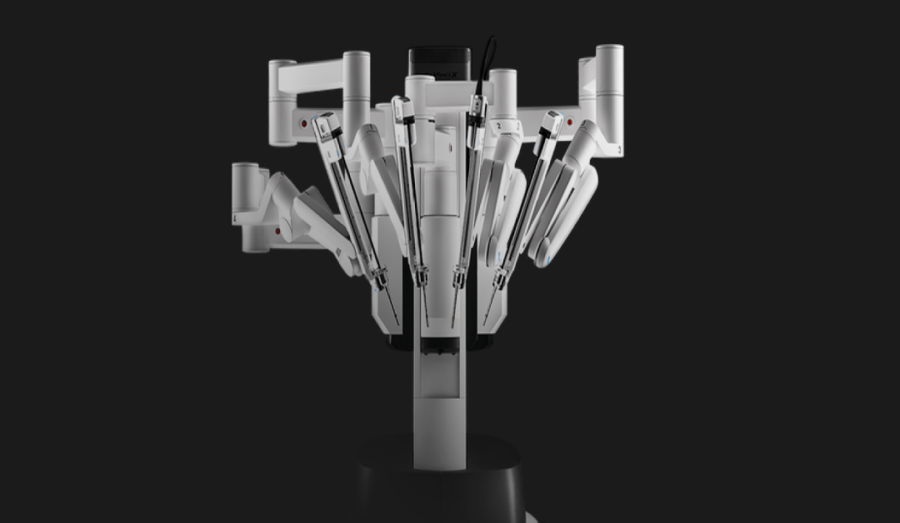

- A virada de chave: o surgimento do Da Vinci

Enquanto a Computer Motion avançava, outra empresa, Intuitive Surgical, desenvolvia seu próprio sistema: o Da Vinci, aprovado pelo FDA em 2000.

Ele oferecia três pilares que mudaram para sempre a cirurgia:

- Visão 3D em alta definição

Algo inexistente na laparoscopia tradicional.

- Instrumentos articulados com pulso robótico (“EndoWrist”)

Permitindo uma liberdade de movimento maior que a da mão humana.

- Ergonomia e estabilidade

O cirurgião opera sentado, com movimentos filtrados, ampliados e estabilizados.

Mais do que inovação, o Da Vinci entregou resultados clínicos consistentes. E isso fez dele praticamente um monopólio por duas décadas: mais de 8.000 sistemas instalados no mundo e milhões de cirurgias realizadas.